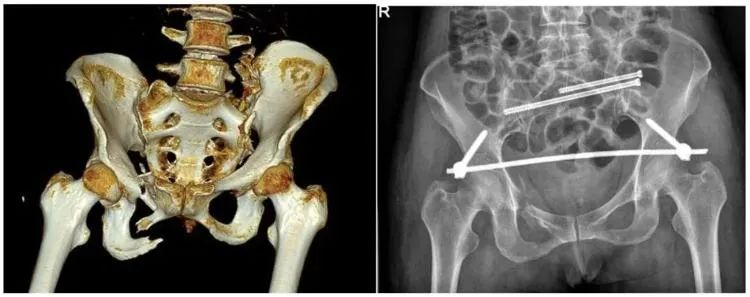

【醫(yī)療科普】:不穩(wěn)定性骨折影像

不穩(wěn)定性骨折

普愛醫(yī)療推出的大平板一體式C形臂PLX119C,配置30cm×30cm平板探測(cè)器,大視野,能夠呈現(xiàn)更多圖像細(xì)節(jié),對(duì)于諸如骨盆雙側(cè)骨折類型手術(shù)或骨盆后環(huán)內(nèi)固定術(shù)具有應(yīng)用優(yōu)勢(shì),一次曝光可獲取全部骨折部位影像,可簡(jiǎn)化曝光流程,提高手術(shù)效率。